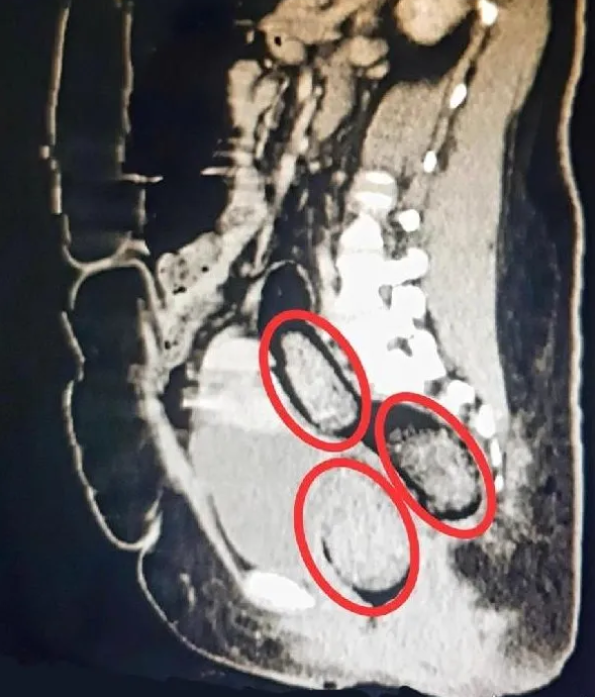

Hastanede çekilen röntgen sonucu makatında 3 parça uyuşturucu olduğu ortaya çıktı. Ekipler şaştı kaldı.

Kars Harakani Devlet Hastanesi'ne götürülen Aeınezad'ın çekilen röntgeninde, makatında uyuşturucu çıktı.

Cerrahi operasyonla kadının makatından 3 parça halinde toplam 318 gram metamfetamin çıkarıldı.